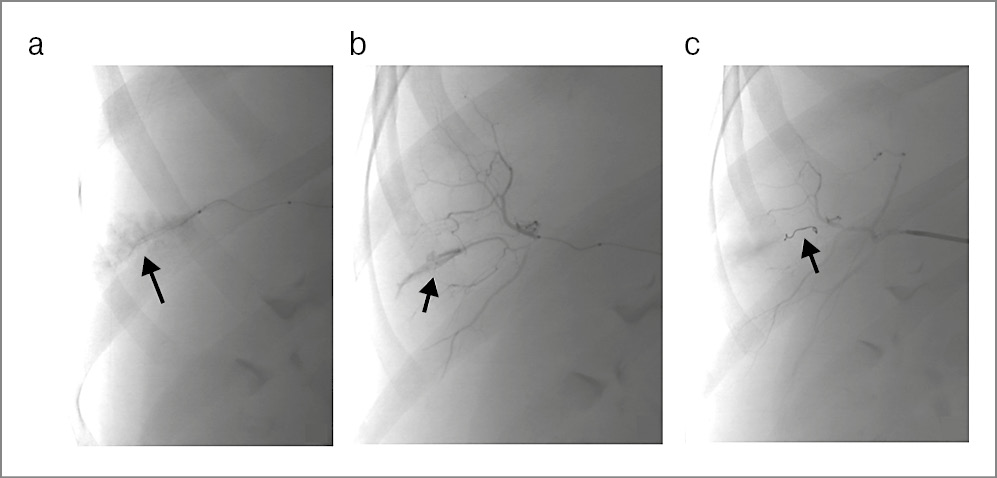

При КТ ОБП с внутривенным контрастированием поддиафрагмально, подпеченочно, межпетельно и в латеральных каналах наблюдалась свободная жидкость. Печень увеличена в размерах: 233×179×210 мм. Контуры четкие, ровные. Плотность паренхимы – 15 едН. В SVI печени при контрастном усилении визуализируется гиповаскулярное образование плотностью жидкости (24 едН) размерами 17×22 мм. При контрастном усилении определяется экстравазация из бассейна правой печеночной артерии. Структуры ворот печени дифференцированы (рис. 1).

Рис. 1. Компьютерные томограммы живота с внутривенным контрастированием: а – гематома SVI печени с экстравазацией контрастного вещества, свободная жидкость над печенью (стрелки); b – свободная жидкость в малом тазу (стрелка).